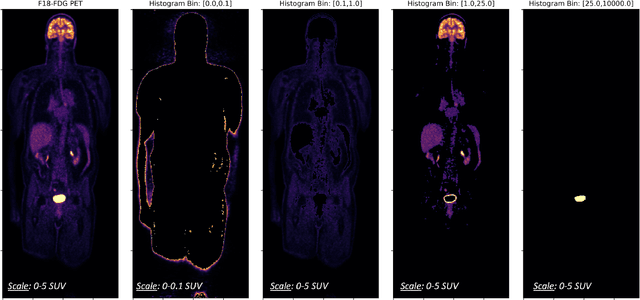

Abstract:Historically, patient datasets have been used to develop and validate various reconstruction algorithms for PET/MRI and PET/CT. To enable such algorithm development, without the need for acquiring hundreds of patient exams, in this paper we demonstrate a deep learning technique to generate synthetic but realistic whole-body PET sinograms from abundantly-available whole-body MRI. Specifically, we use a dataset of 56 $^{18}$F-FDG-PET/MRI exams to train a 3D residual UNet to predict physiologic PET uptake from whole-body T1-weighted MRI. In training we implemented a balanced loss function to generate realistic uptake across a large dynamic range and computed losses along tomographic lines of response to mimic the PET acquisition. The predicted PET images are forward projected to produce synthetic PET time-of-flight (ToF) sinograms that can be used with vendor-provided PET reconstruction algorithms, including using CT-based attenuation correction (CTAC) and MR-based attenuation correction (MRAC). The resulting synthetic data recapitulates physiologic $^{18}$F-FDG uptake, e.g. high uptake localized to the brain and bladder, as well as uptake in liver, kidneys, heart and muscle. To simulate abnormalities with high uptake, we also insert synthetic lesions. We demonstrate that this synthetic PET data can be used interchangeably with real PET data for the PET quantification task of comparing CT and MR-based attenuation correction methods, achieving $\leq 7.6\%$ error in mean-SUV compared to using real data. These results together show that the proposed synthetic PET data pipeline can be reasonably used for development, evaluation, and validation of PET/MRI reconstruction methods.